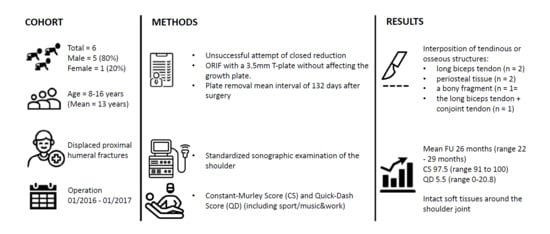

Between January 2016 and January 2017, 21 skeletally immature patients with proximal humeral fractures were treated at the authors institute (level 1 trauma hospital). Six of these patients (29%) were treated by open reduction and internal fixation. All of these six patients were included in the study.

The inclusion criteria were: available standard x-rays in anteroposterior (AP) and Neer view preoperatively and 6 weeks postoperatively, severely displaced humeral fracture (Neer–Horwitz III/IV), not reducible by closed means, open physis and hardware removal performed. After 2 years, patients were prospectively assessed with a clinical and sonographic examination. Informed consent was obtained from the patient’s or her/his legal representative.

2.1. Surgical Technique

All of the operative procedures were carried out under general anesthesia. The patients were positioned in beach chair position. An initial attempt of closed reduction was conducted in all patients. This was performed by gentle longitudinal traction with abduction and external rotation of the arm. An image intensifier was used to monitor reduction. If closed reduction failed, the surgeon proceeded with open reduction by means of an anterior deltopectoral approach. Entrapped tissue or periosteum were gently freed. Once reduction was achieved, a 3.5 mm T-plate was contoured on the anterolateral part of the proximal humerus and temporary K-wires were inserted through the plate holes to hold the reduction. Under image intensifier, attention was drawn not to injure the physeal plate by the drill or the screws. After confirming anatomical reduction, the K-wires were then replaced with conventional cortical screws.

Figure 1A,B). In these six patients, a closed reduction was attempted; in five patients, an immediate conversion to open surgery with open reduction and internal plate fixation was necessary.

For this patient, it was apparent that a closed reduction was impossible due to the interposition of soft tissue at the fracture site. Tissue entrapment was intraoperatively observed in all of the six cases (the long biceps tendon in two cases (Pat. N° 1 and 5), periosteal tissue in two cases (Pat. N° 3 and 6), a bony fragment in one case (Pat. N° 4), and both the long biceps tendon as well as the conjoint tendon in one case (Pat. N° 4)) (

The scheduled removal of the hardware was performed in all six patients. The implants were removed under general anesthesia as a day case procedure without difficulty at a mean time of 4.4 months after surgery (range 3–5.3 months).

Table 1). The Constant–Murley score at the final follow-up was 97.5 (range 91 to 100) and the mean overall QuickDASH score (including sport and music/work) was 5.5 (range 0–20.8). Analyzing the subtypes of the QuickDASH score, we found a score of 3 for disability (range 0–10), 3.125 for sport and music (range 0–12.5) and 0 for work.

A sonographic examination of the shoulder two years postoperatively showed normal rotator cuff, long head of biceps and conjoint tendon (